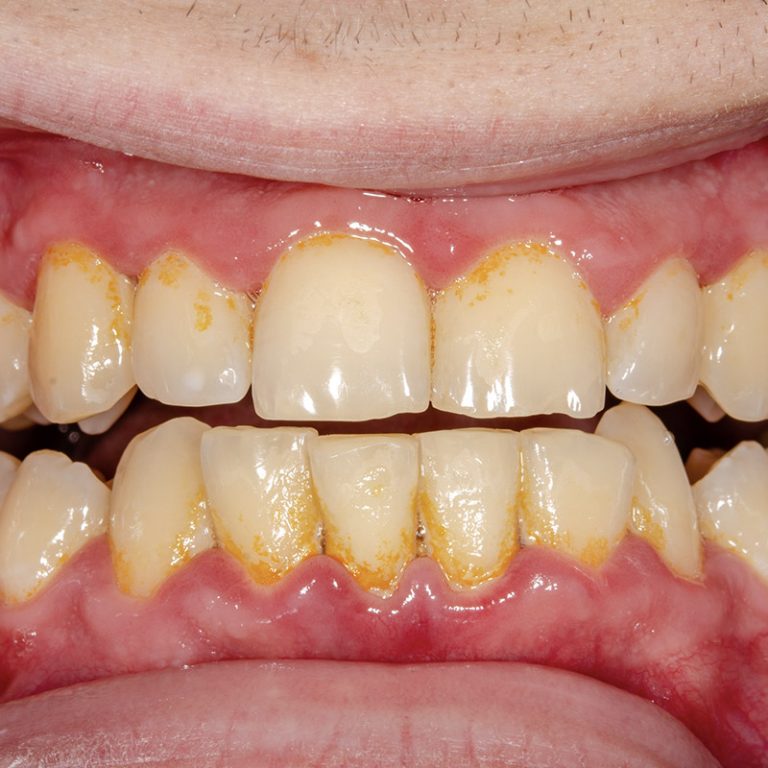

gingivite zahnstein gencives prophylaxe dentalhygiene smell dentaire zahnarztpraxis entstehung parodontite maladie luzern poop traitements une inflammation smells behandlung vorbeugung vorher zahnstein zahnarzt